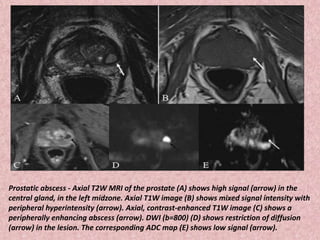

Prostatic abscess - Axial T2W MRI of the prostate (A) shows high signal (arrow) in the

central gland, in the left midzone. Axial T1W image (B) shows mixed signal intensity with

peripheral hyperintensity (arrow). Axial, contrast-enhanced T1W image (C) shows a

peripherally enhancing abscess (arrow). DWI (b=800) (D) shows restriction of diffusion

(arrow) in the lesion. The corresponding ADC map (E) shows low signal (arrow).

Prostatic abscess -Axial T2W MRI of the prostate (A) shows high signal (arrow) in the central gland, in the left midzone. Axial T1W image (B) shows mixed signal intensity with peripheral hyperintensity (arrow). Axial, contrast-enhanced T1W image (C) shows a peripherally enhancing abscess (arrow). DWI (b=800) (D) shows restriction of diffusion (arrow) in the lesion. The corresponding ADC map (E) shows low signal (arrow).